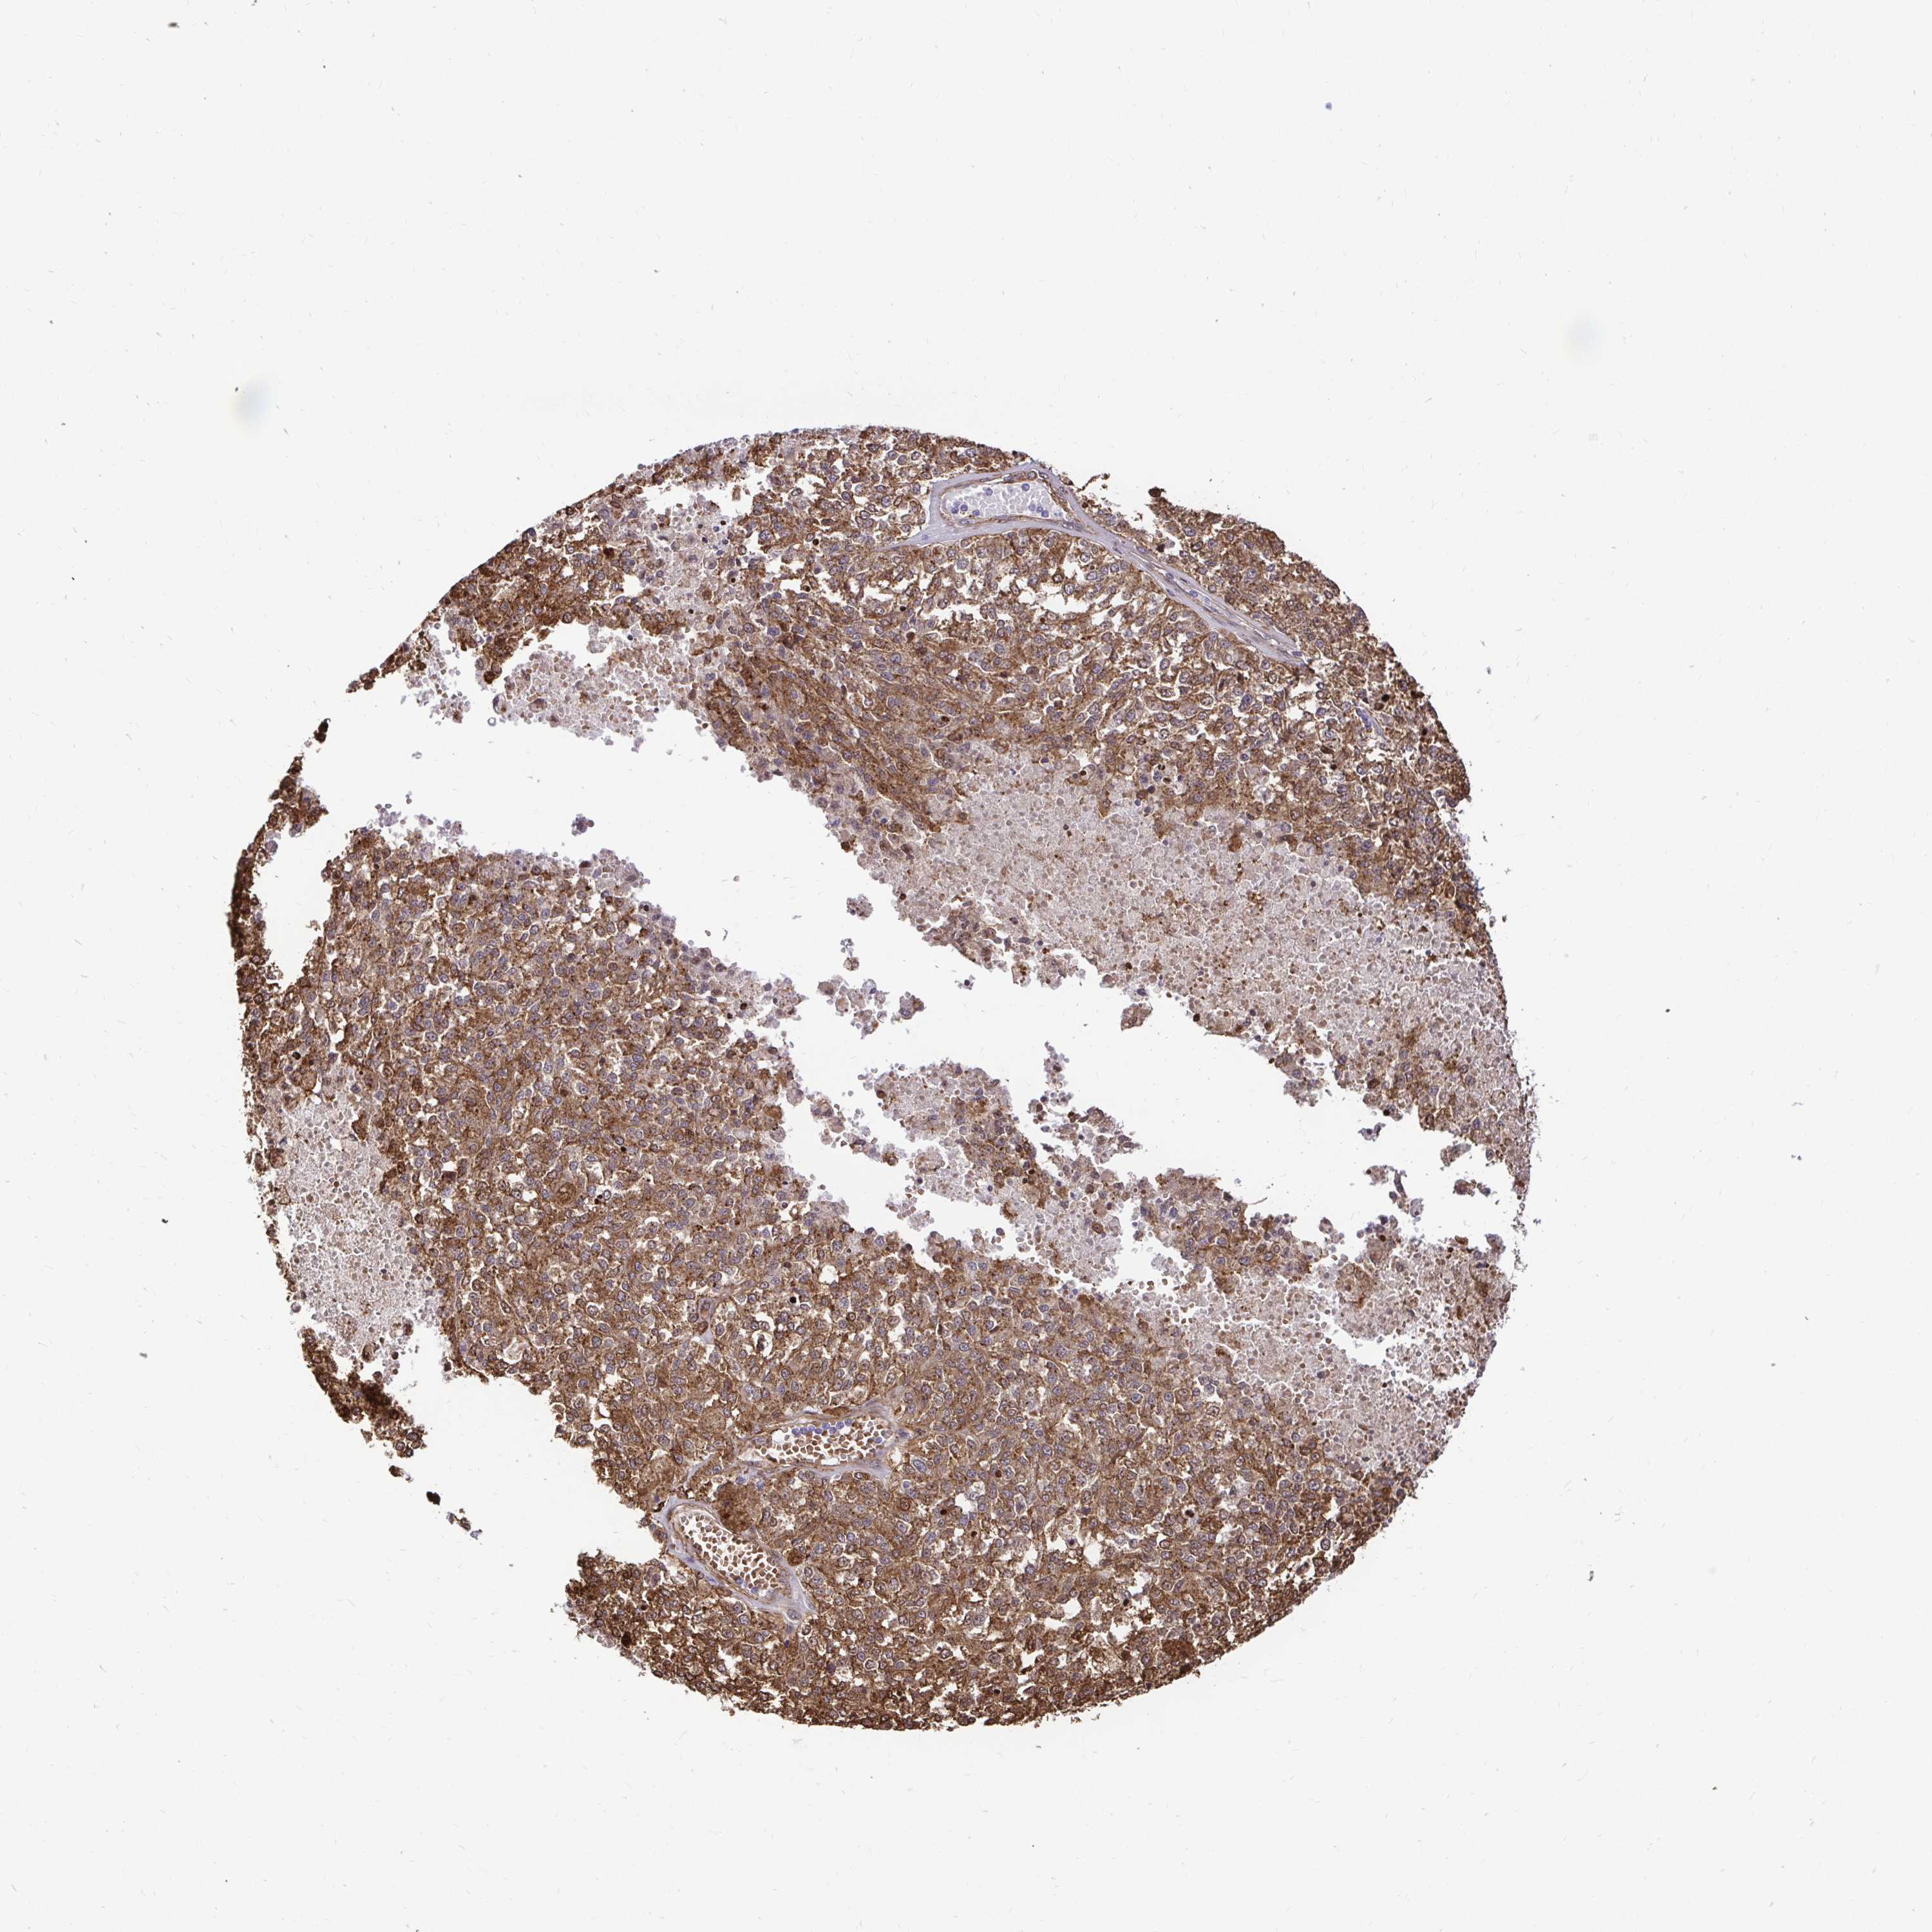

MELANOMA - Protein expressioni

A mouse-over function shows sample information and annotation data. Click on an image to view it in a full screen mode. Samples can be filtered based on level of antibody staining by selecting one or several of the following categories: high, medium, low and not detected. The assay and annotation is described here.

Note that samples used for immunohistochemistry by the Human Protein Atlas do not correspond to samples in the TCGA dataset.

Antibody stainingi

Antibody staining in the annotated cell types in the current human tissue is reported as not detected, low, medium, or high, based on conventional immunohistochemistry profiling in selected tissues. This score is based on the combination of the staining intensity and fraction of stained cells.

Each image is clickable and will lead to virtual microscopy that enables deeper exploration of all samples and also displays staining intensity scores, fraction scores and subcellular localization as well as patient and tissue information for each sample.

Antibody HPA054026

Antibody CAB010823

Antibody CAB016728

Antibody CAB036009

Staining

High

Medium

Low

Not detected

Intensity

Strong

Moderate

Weak

Negative

Quantity

>75%

75%-25%

<25%

None

Location

Nuclear

Cytoplasmic/membranous

Cytoplasmic/membranous,nuclear

Malignant melanoma, Metastatic site

Malignant melanoma, NOS